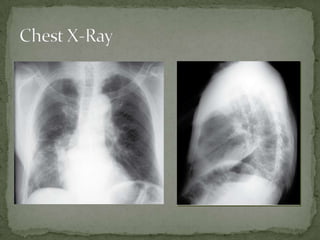

A 76-year-old female presented with worsening dyspnea, cough producing yellow sputum, subjective fevers and chills, weakness and decreased appetite. Her vital signs and physical exam showed signs of infection. Chest x-rays revealed consolidation in the right middle lobe, suggesting lobar pneumonia. She was treated with oxygen, IV fluids, antibiotics and admitted to the hospital based on her condition.